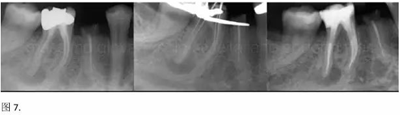

開髓后預敞、探查根管、建立直線通路是根管機械預備的第一步。在這些階段中,醫(yī)生可能會經常遇到一些困難。這些難題包括器械折斷、臺階形成、根管歧坡或根管拉直、帶狀穿孔、根尖穿孔、根尖肘形、根尖堵塞。所有這些錯誤可導致根管系統(tǒng)清潔不完善從而降低牙髓治療成功率。

本文的目的是描述一種旨在優(yōu)化根管根尖部分預備的預敞技術。根管頸部或冠方的早期預敞對于減少初尖銼直徑和根尖部根管直徑之間的差異至關重要。大量研究表明,手用或機用器械預敞根管能顯著減少器械折斷的發(fā)生率。